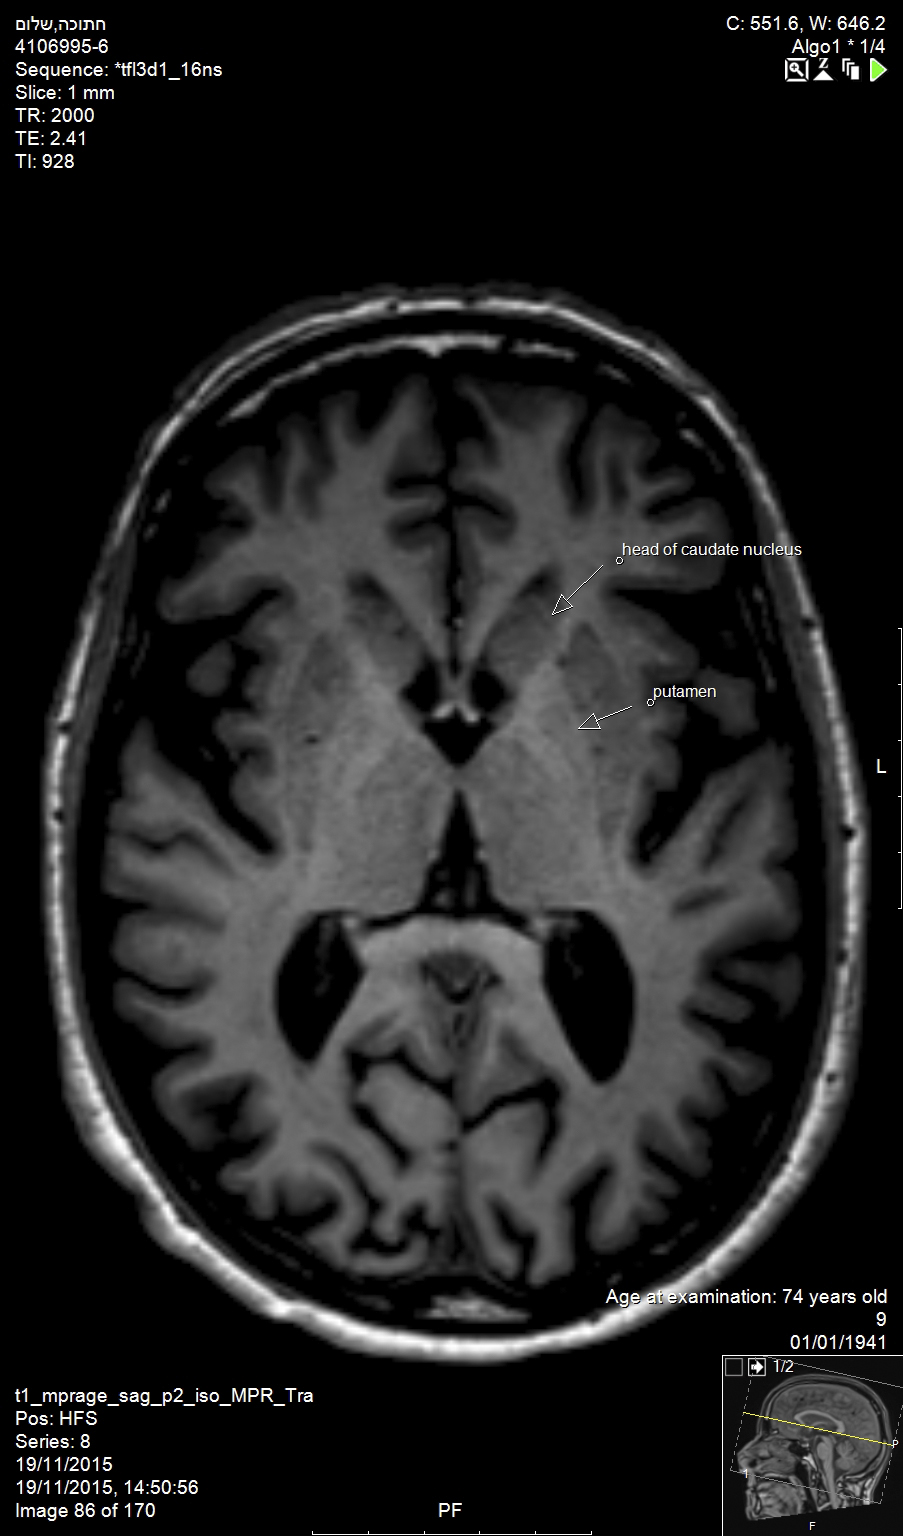

In the brain, Alzheimer’s disease and Huntington’s disease result in widespread loss of neurons (Figure 1), while Parkinson’s disease involves the specific and localized loss of dopaminergic neurons in the substantia nigra. In the brainstem and spinal cord, amyotropic lateral sclerosis and spinal muscular atrophy involve the degeneration and loss of motor neurons. While all of these conditions exhibit unique neuronal pathologies, the exact mechanisms for neuronal loss are complex, making the identification of efficacious treatments elusive.1

Huntington’s disease is named after George Huntington, the physician who described it as hereditary chorea in 1872. It is an incurable, adult-onset, autosomal dominant inherited disorder associated with cell loss within a specific subset of neurons in the basal ganglia and cortex.3 The most striking neuropathology in Huntington’s disease occurs within the neostriatum (Figure 2), in which gross atrophy of the caudate nucleus and putamen (Figure 3) is accompanied by selective neuronal loss and astrogliosis. Marked neuronal loss is also seen in deep layers of the cerebral cortex.4 The clinical features include a movement disorder, cognitive disorder, dementia, and behavior disorder. Patients may present with one or all disorders in varying degrees.5

Fig 1. Alzheimer’s disease and Huntington’s disease result in widespread loss of neurons, as shown in this magnetic resonance image (MRI) of the brain of an elderly patient (top arrow: head of caudate nucleus; bottom arrow: putamen).

Figure 1